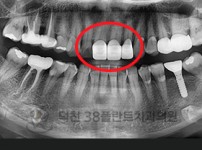

치료전후